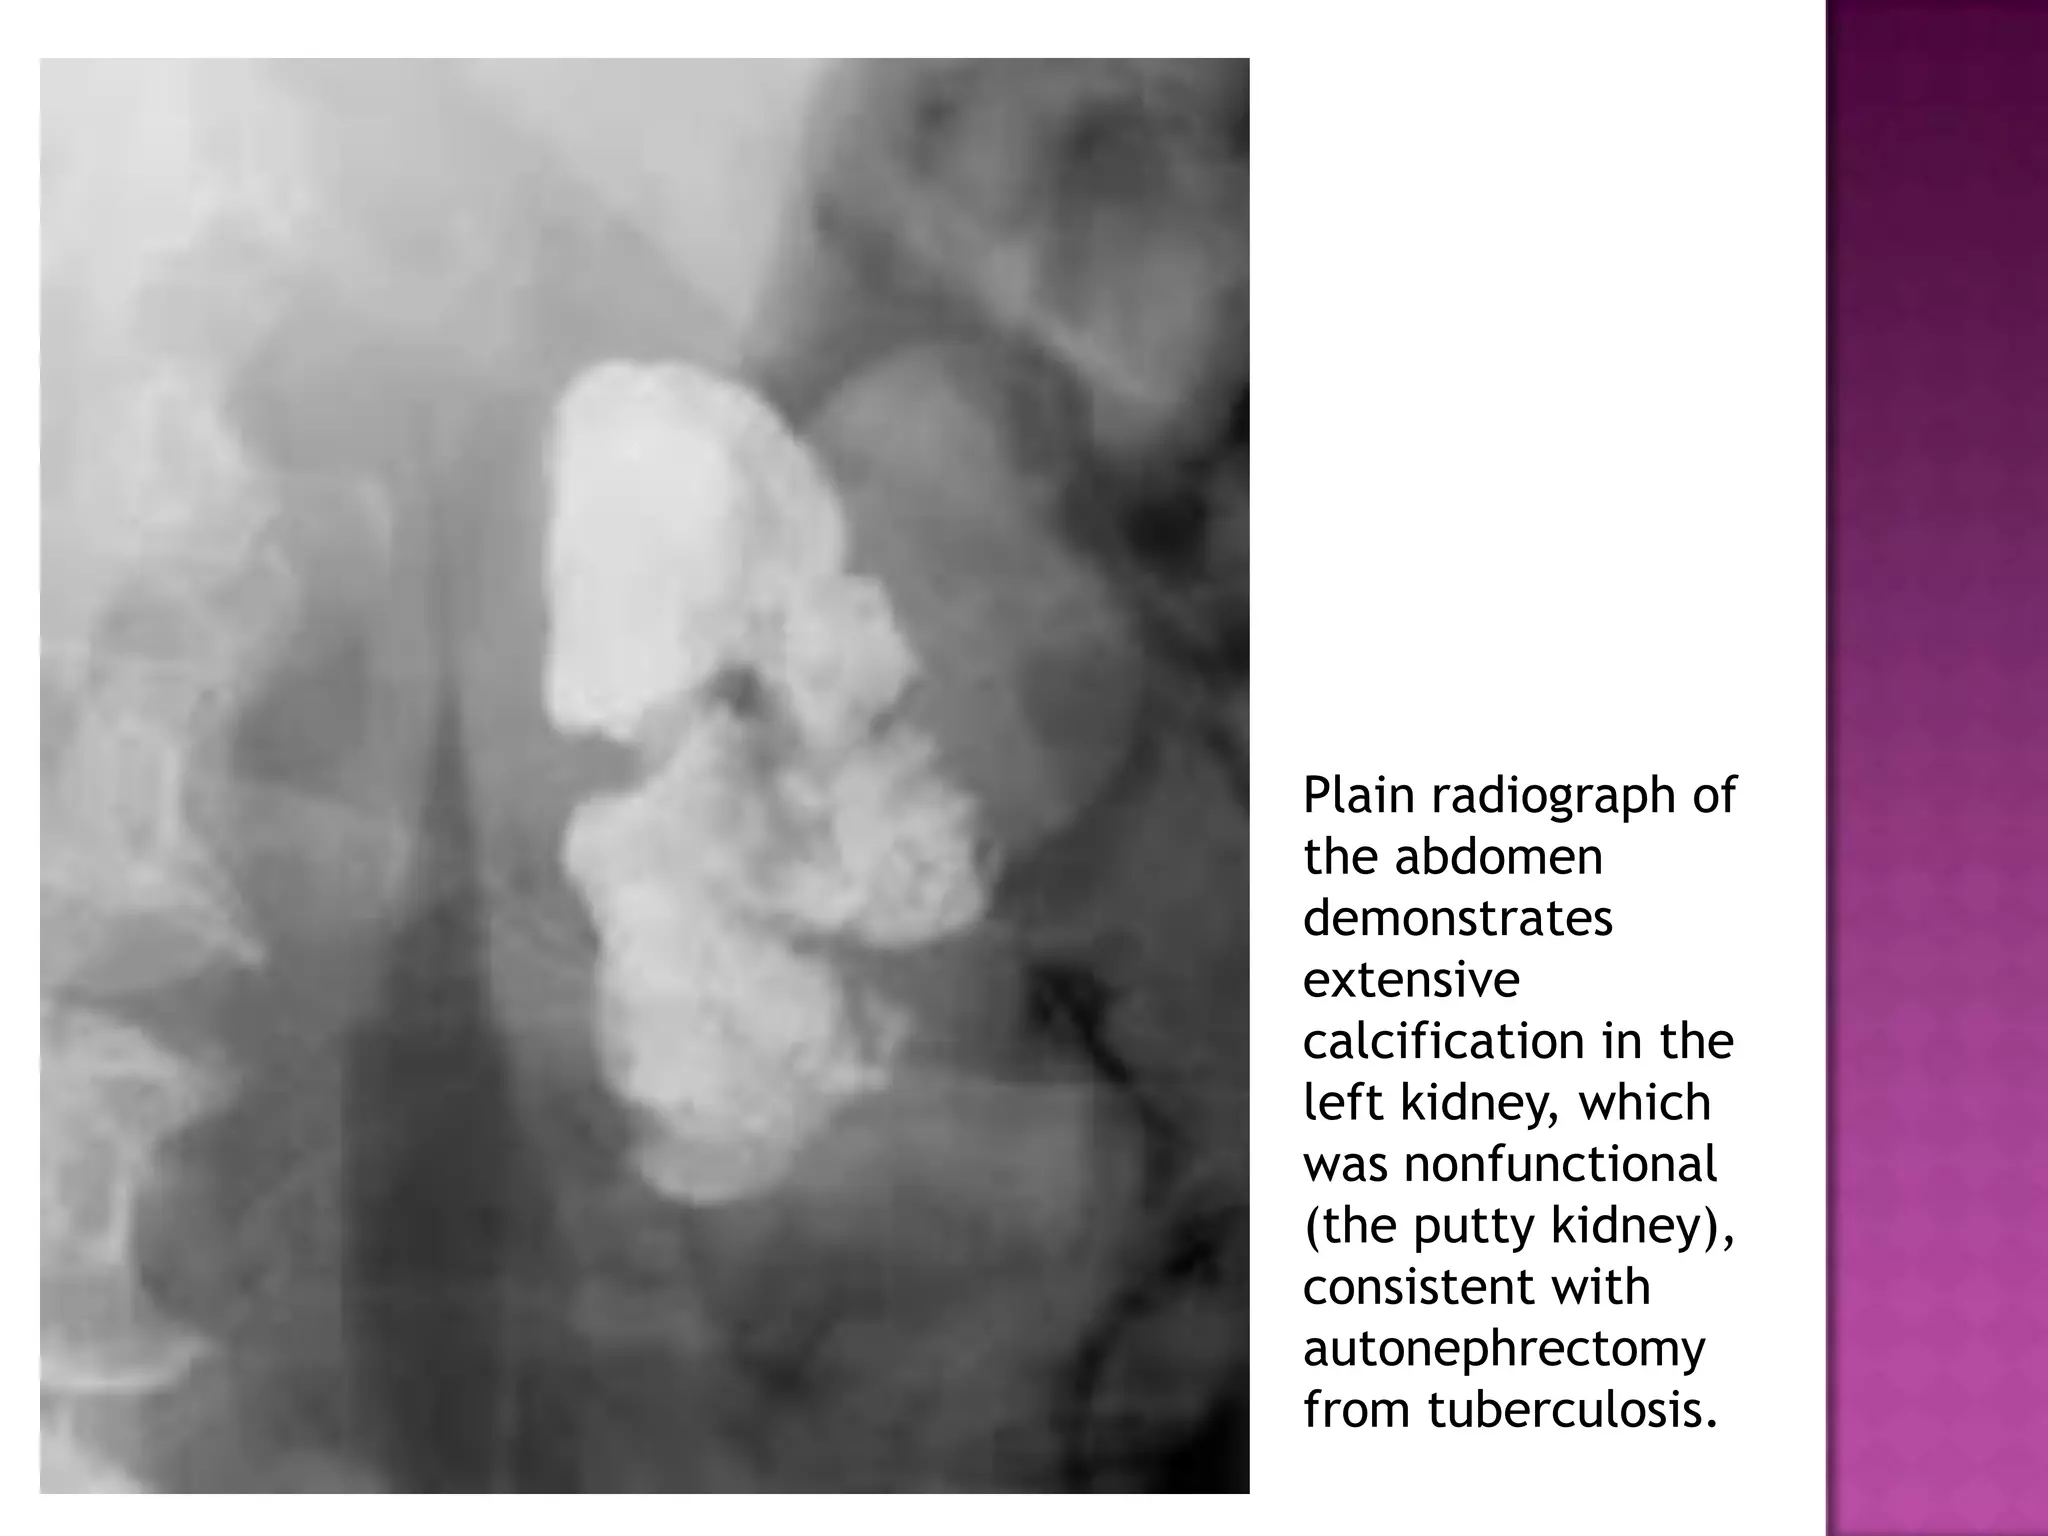

Plain radiograph of

the abdomen

demonstrates

extensive

calcification in the

left kidney, which

was nonfunctional

(the putty kidney),

consistent with

autonephrectomy

from tuberculosis.